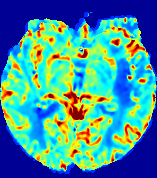

LesionRefer to captionRefer to captionRefer to captionRefer to captionRefer to captionRefer to caption𝐕rgbsubscript𝐕𝑟𝑔𝑏{\bf{V}}_{rgb}Refer to captionRefer to captionRefer to captionRefer to captionRefer to captionRefer to caption𝐕2subscriptnorm𝐕2{\|\bf{V}}\|_{2}Refer to captionRefer to captionRefer to captionRefer to captionRefer to captionRefer to captionRefer to caption3.53.53.52.82.82.82.12.12.11.41.41.40.70.70.70.00.00.0(mm/s)𝑚𝑚𝑠(mm/s)D𝐷DRefer to captionRefer to captionRefer to captionRefer to captionRefer to captionRefer to captionRefer to caption0.0200.0200.0200.0160.0160.0160.0120.0120.0120.0080.0080.0080.0040.0040.0040.0000.0000.000(mm2/s)𝑚superscript𝑚2𝑠(mm^{2}/s)Slice #1Slice #2Slice #3Slice #4Slice #5Slice #6

Figure 3: PIANO feature maps for one stroke patient, where the lesion is located in the left hemisphere. Top row: segmented stroke lesion region (white) on different slices, obtained from ISLES 2017. The corresponding slices for the PIANO feature maps are shown in the following rows.

For a better insight into an estimated velocity field 𝐕𝐕{\bf{V}} and diffusion field 𝐃𝐃{\bf{D}}, we compute the following maps: (1) 𝐕rgbsubscript𝐕𝑟𝑔𝑏{\bf{V}}_{rgb}: Color-coded orientation map of 𝐕=(Vx,Vy,Vz)T𝐕superscriptsuperscript𝑉𝑥superscript𝑉𝑦superscript𝑉𝑧𝑇{\bf{V}}=(V^{x},V^{y},V^{z})^{T}, obtained by normalizing 𝐕𝐕{\bf{V}} to unit length and mapping its 3 components to red, green, blue respectively; (2) 𝐕2subscriptnorm𝐕2\|{\bf{V}}\|_{2}: 222 norm of 𝐕𝐕{\bf{V}}; (3) D𝐷D: scalar field in Eq. 5.

Fig. 3 and Fig. 4 show the PIANO feature maps estimated from two ISLES 2017 patients: all are highly consistent with the lesion in both cases. Details of the blood flow trajectories are revealed in 𝐕rgbsubscript𝐕𝑟𝑔𝑏{\bf{V}}_{rgb} by the ridged patterns and the sharp changes of colors in the unaffected (right) hemisphere, while the flat patterns appearing within the lesion provide little directional information about the velocity and indicate low velocity magnitudes. Velocity magnitudes are more directly visualized via 𝐕2subscriptnorm𝐕2\|{\bf{V}}\|_{2}, from which one can easily locate the lesion where 𝐕2subscriptnorm𝐕2\|{\bf{V}}\|_{2} is low. D𝐷D also indicates lower diffusion values in the lesion, though with less contrast potentially due to the fact that it captures the accumulated effect of CA diffusion at the voxel-level.